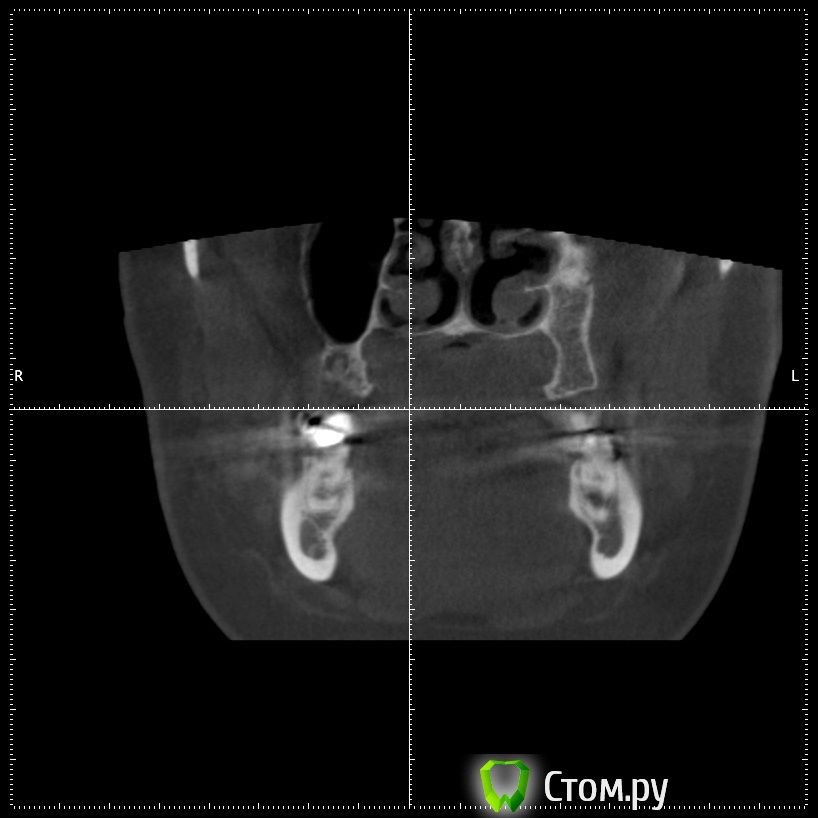

stommm Опубликовано 17 сентября, 2014 Поделиться Опубликовано 17 сентября, 2014 Всем доброго времени суток) Ко мне обратилась пациентка с жалобами на отсутствие зубов во втором сегменте. Сделала кт. Честно говоря такого кт я еще не видел.Что это, господа, вариант нормы или признак патологии? Встречалось ли подобное в вашей практике? Планирую нарастить по ширине и имплантировать, без синуса. Ссылка на комментарий

Bier Опубликовано 18 сентября, 2014 Поделиться Опубликовано 18 сентября, 2014 тут просто пазуха заросла костью, природа сделала синуслифтинг )) 2 Ссылка на комментарий

stommm Опубликовано 18 сентября, 2014 Автор Поделиться Опубликовано 18 сентября, 2014 По данным литературы, в 7-10% случаев может наблюдаться асиметрия пазух (пневматизированная/склерозированная)Я думаю здесь не просто одна пазуха более пневматизированная чем иная. Полость носа тоже кажется довольно несимметричной. тут просто пазуха заросла костью, природа сделала синуслифтинг ))А то что ширина самих пазух отличается сильно, это нормально? Ссылка на комментарий

Alexey Doc Опубликовано 18 сентября, 2014 Поделиться Опубликовано 18 сентября, 2014 Гипоплазия левой гайморовой пазухи. У самого было 2-е похожих пациентов 2 Ссылка на комментарий

dr-krasnov Опубликовано 6 октября, 2014 Поделиться Опубликовано 6 октября, 2014 Гипоплазия левой гайморовой пазухи. У самого было 2-е похожих пациентов Верный ответ. 1 Ссылка на комментарий